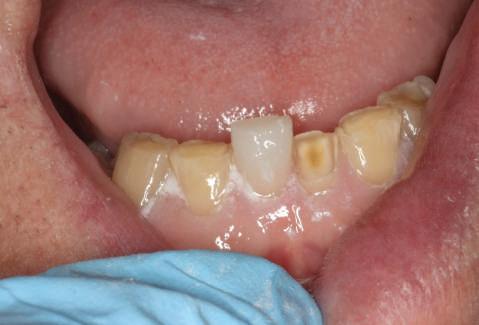

Şapte luni mai târziu (fig. 2), acele bonturi individualizate din prima etapă au manifestat semne de recesie de 1-3mm. Atitudine: S-a decis reprepararea intraorală a tuturor bonturilor (fig. 3), astfel încât toate marginile bonturilor să fie la nivelul sau sub marginea gingivală (de notat că 1.1. şi 2.1. au fost submersaţi ulterior pentru a avea sprijin implantar deplin).

Cazul (1): Reprepararea intraorală a bonturilor Figurile

2. După 7 luni, bonturile individualizate din prima etapă au prezentat recesie de 1-3mm.

3. Bonturile repreparate intraoral.